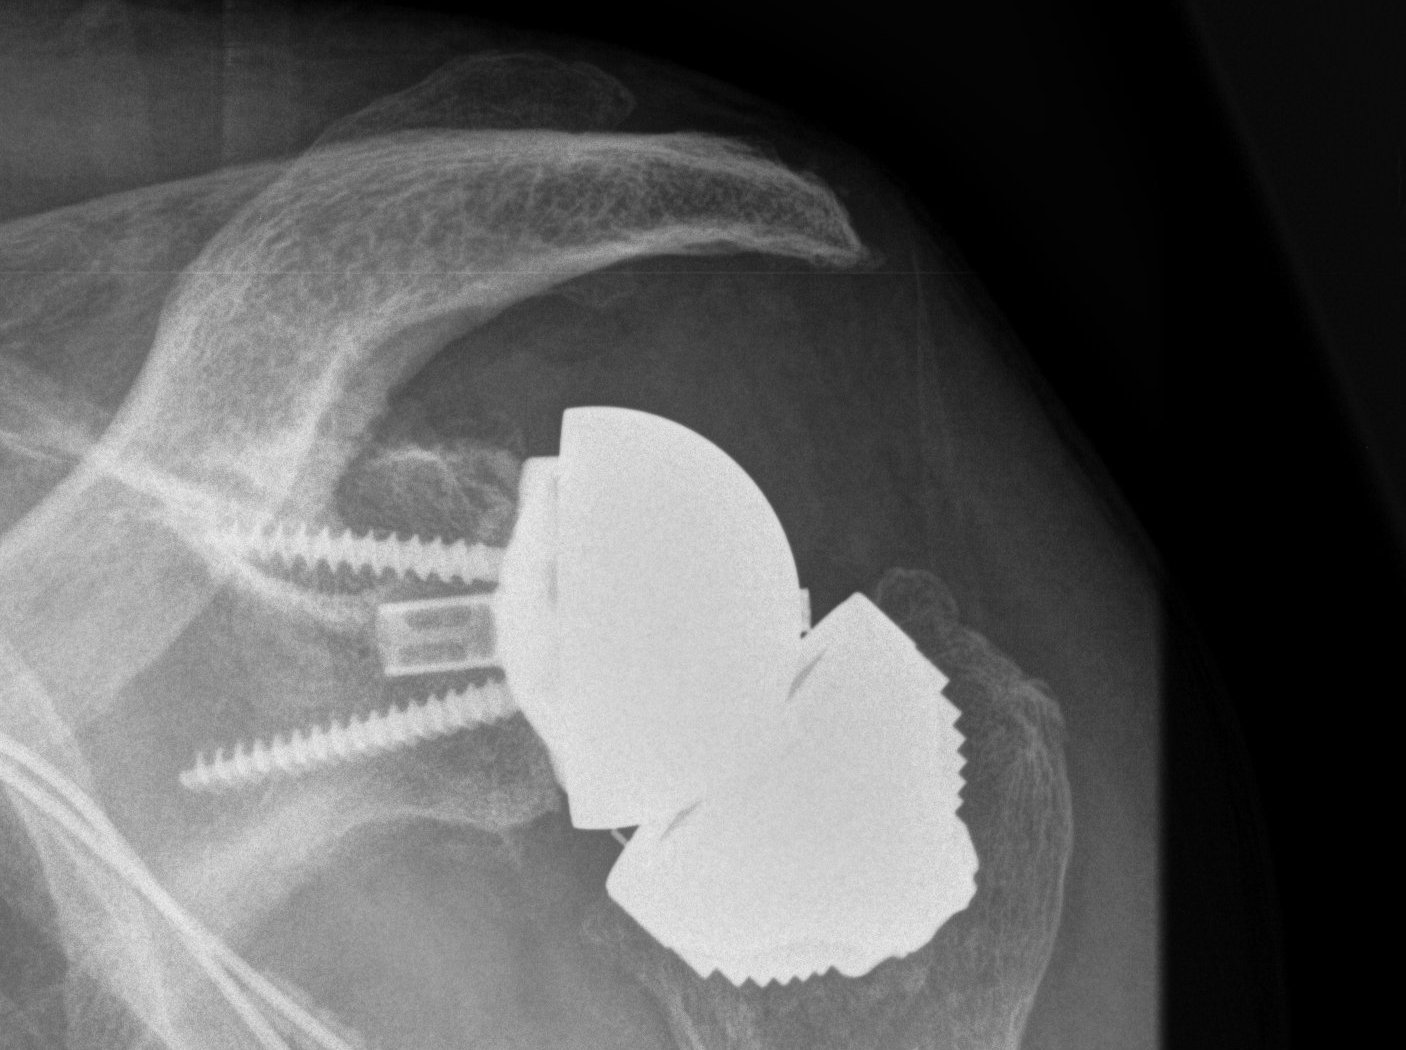

Inferior scapula notching

NotchingGlenosphere overhang

Scapula notching.  Prevented by inferior glenosphere overhand (Depuy Synthes Delta Xtend)

Mechanism

Impingement of humerus component on scapular neck

With arm in extension / adduction / external rotation

Prevention

Glenosphere position

- inferior hang - eccentric glenosphere design

- inferior tilt

- lateralization